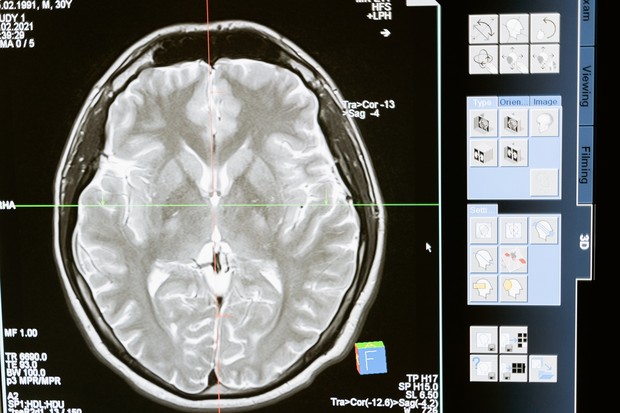

Tumor Otak

Melansir dari Cancer.org, kanker otak juga menjadi salah satu kanker yang sering menyerang anak-anak, yakni sebanyak 26 persen. Kanker otak sering kali dimulai dari bagian bawah otak, seperti otak kecil atau batang otak. Beberapa gejala kanker otak dapat dideteksi melalui tanda-tanda seperti sakit kepala, mual, muntah, penglihatan yang kabur, pusing, kejang, hingga kesulitan berjalan atau memegang benda.